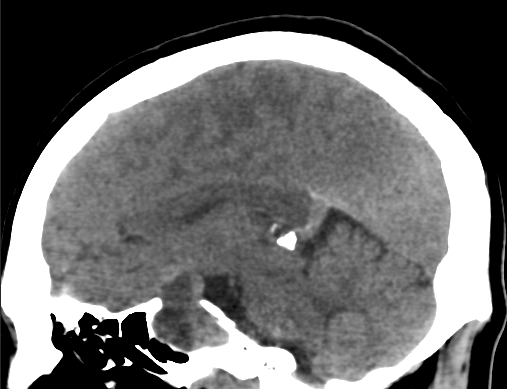

脑积水

垂体腺瘤中的脑积水是由于肿瘤上突扩展而阻塞三脑室的结果。垂体瘤切除后可能因脑室内出血而发展,随后因脑膜炎而发展。我们在2.3%的患者中观察到了这种并发症。这种并发症只限于库欣集团。我们对此没有任何解释。其他患者中没有这种并发症强调了这样一个事实,即手术的大小和持续时间都不是手术发生的原因。